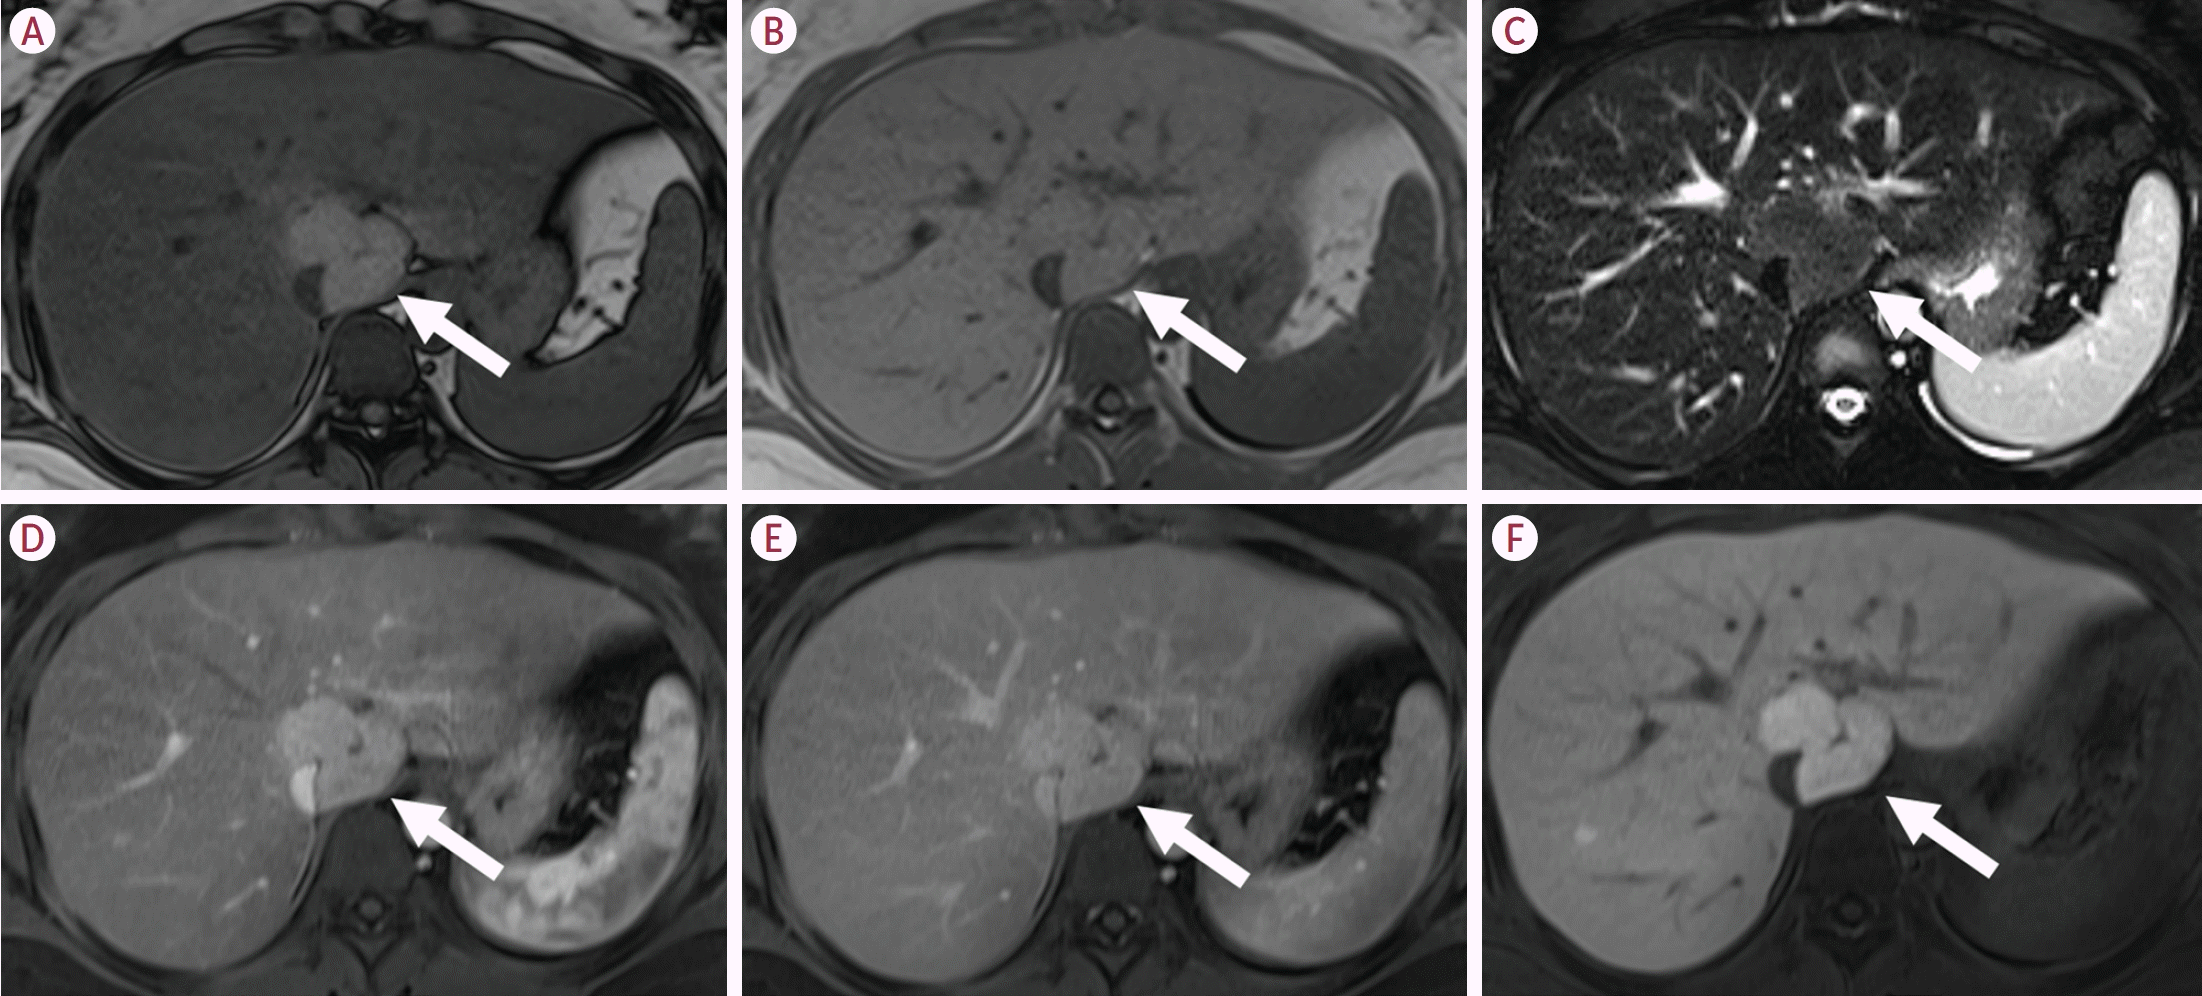

12. Reizine E, Amaddeo G, Pigneur F, Baranes L, Legou F, Mulé S, et al. Quantitative correlation between uptake of Gd-BOPTA on hepatobiliary phase and tumor molecular features in patients with benign hepatocellular lesions. Eur Radiol. 2018; 28:4243–4253.

13. Reizine E, Ronot M, Ghosn M, Calderaro J, Frulio N, Bioulac-Sage P, et al. Hepatospecific MR contrast agent uptake on hepatobiliary phase can be used as a biomarker of marked β-catenin activation in hepatocellular adenoma. Eur Radiol. 2021; 31:3417–3426.

14. Zulfiqar M, Sirlin CB, Yoneda N, Ronot M, Hecht EM, Chernyak V, et al. Hepatocellular adenomas: understanding the pathomolecular lexicon, MRI features, terminology, and pitfalls to inform a standardized approach. J Magn Reson Imaging. 2020; 51:1630–1640.

23. Kim TH, Woo S, Ebrahimzadeh S, McInnes MDF, Gerst SR, Do RK. Hepatic adenoma subtypes on hepatobiliary phase of gadoxetic acid-enhanced MRI: systematic review and meta-analysis. AJR Am J Roentgenol. 2023; 220:28–38.

50. Reizine E, Ronot M, Pigneur F, Purcell Y, Mulé S, Burgio MD, et al. Iso- or hyperintensity of hepatocellular adenomas on hepatobiliary phase does not always correspond to hepatospecific contrast-agent uptake: importance for tumor subtyping. Eur Radiol. 2019; 29:3791–3801.